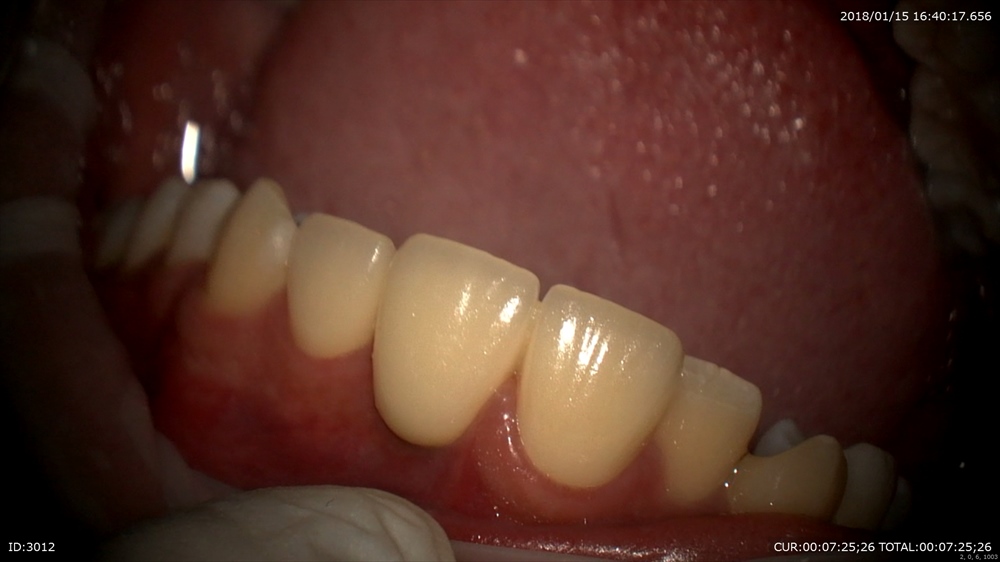

1ケース目

「ブリッジを前回いれて少ししみる。噛むと少し痛い。」

不安になっていました。

不安を解消するために、生きている歯を一周削るブリッジの治療の弱点をマイクロスコープの実際のこの患者さまの施術シーンを振り返りました。すべて録画し日にち別で保管しているからすぐ出来る設備です。

今日

フィットは問題なし

ここから今回のこの画像(動画)と今までの治療を時系列で比較します。

こんなに削るのですね。と関心されていました。見ないと解りませんものね。

このようにすべて動画でお見せし、痛みの可能性やこれからの注意事項をお話できます。当院に来院している皆様に行っていますので通院中の方は良く見る画像ですよね。安心してお帰りになりました。ホッとしました。